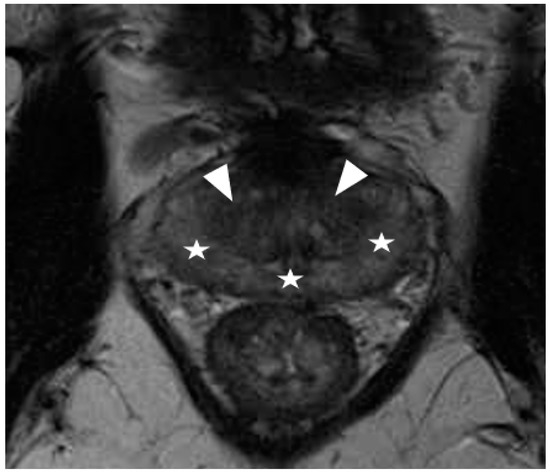

2.5.1. EPE Prediction